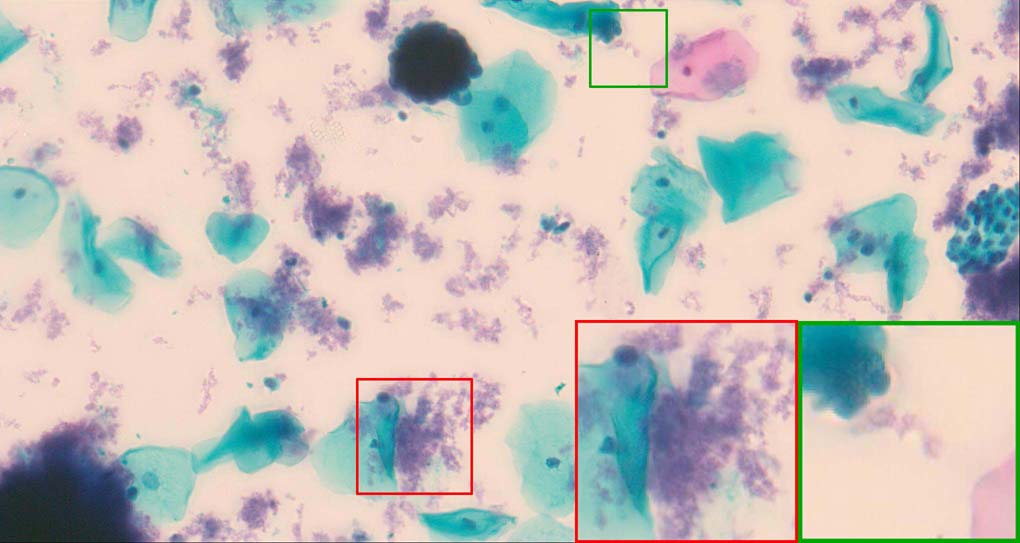

To demonstrate the effectiveness and efficiency of the proposed image fusion method , we conduct a set of comparative experiments on three image datasets. The first is composed by 8 pairs of multi-modal medical images and the second one contains 15 pairs of multi-focus gray or color natural images. These two datasets are often used in many related papers and some examples are shown in Figure 3(a) and Figure 3(b). The third one is a new multi-focus cervical cell image dataset collected by ourselves, which consists of 15 groups of color images and each group contains a series of multi-focus cervix cell images with size of or , etc. Some source examples are shown in Figure 3(c). Our source code implemented in C++ along with the new multi-focus cervical cell image dataset is available online.

Figure 9, Figure 10 and Figure 11 show the comparative fused results of the multi-focus cell images shown in Figure 3(c). For clarity, we also present a closeup view in the right-bottom of each sub-picture in Figure 9 and Figure 10. As shown in the close-up views of Figure 9, the fused images based on DSIFT, IM, MWGF and BF methods are extremely blurred in the boundary and fail to keep the details of cell nucleus. Furthermore, the DTCWT and NSCT based methods produce halo artifacts in the fused images, while GFF and CNN based methods fail to preserve the small cell nucleus. LP-SR based method nearly works fine which keeps the most of the details of the small size cells, but the integrity of the clustered large size cells is damaged. Fortunately, in our proposed method, the integrity of the clustered large size cells is preserved and most of the isolated small size cells are maintained from the original images, which demonstrates the best visual quality.

Similarly, as shown in the close-up views of Figure 10, the fused images from DSIFT, IM, MWGF and BF are blurred and lose some nucleus details, while the results from DTCWT, GFF, CNN and NSCT produce halo artifacts. LP-SR based method can keep details well but also produces halo artifacts and other noise. Our method can preserve the focused areas of different source images well without introducing any artifacts. For the example illustrated in Figure 11, the fused images generated by DSIFT, DTCWT, IM and NSCT all fail to preserve the focused areas of different source images and result in extremely blurred images. The GFF, CNN, MWGF and BF based method introduces a lot of color distortion of the nucleus regions and the obvious halo artifact. The result of LP-SR based method is close to the one of our method but introduces some odd color distortion. Again, our method produces fused image which can preserve the focused areas of different source images well without introducing any artifacts.